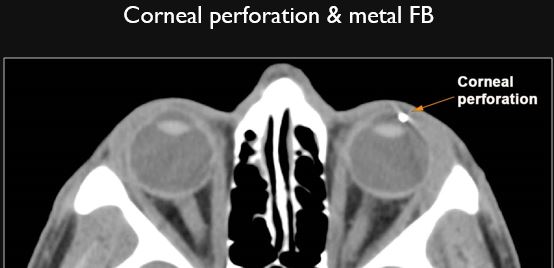

There is a slightly or obviously radiodense foreign body in areas of soft tissue swelling or elsewhere. [Yes/No]

There is an air (low density) pattern, either a tract or “geometrically shaped”, suggestive of a penetrating injury in areas of soft tissue swelling or elsewhere. [Yes/No]